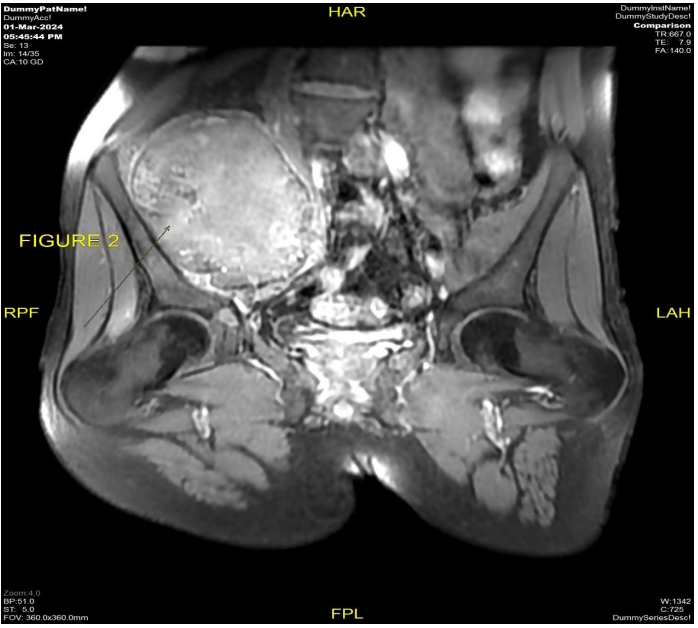

The patient underwent MRI pelvis (Fig 1 & 2) and PETCT (Fig 3 & 4) for initial evaluation (03/2024) at our institute which showed ill-defined large altered signal intensity heterogeneously enhancing mass in the right lumbar region with both intra as well as intrapelvic component by causing erosion of the right iliac bone involving the adjacent iliopsoas and gluteus muscles with central necrosis. On PET-CT scan the lesion showed significant FDG uptake with no other abnormality in the rest of the scan. Text the patient was planned for neoadjuvant chemotherapy and then for surgery. Patient took 2 cycles of neoadjuvant chemotherapy (Holoxan and Adriamycin), but after 2 cycles of chemotherapy response evaluation MRI was done (01/07/2024) (Fig 5) which showed increase in the size of lesion, so patient was planned for targeted therapy ie tyrosine kinase inhibitors, Pazopanib.

Figure 1 & 2: MRI pelvis dated 03/2024 axial and coronal view T1 post-contrast sequence shows ill-defined heterogeneously enhancing necrotic mass measuring approximately 9.8 cm in AP dimension is seen involving the right lumbar and pelvic region causing erosion of the adjacent right iliac bone and transverse process of S1 and S2 Vertebrae with both intra as well as extrapelvic component.

Figure 1

Figure 2